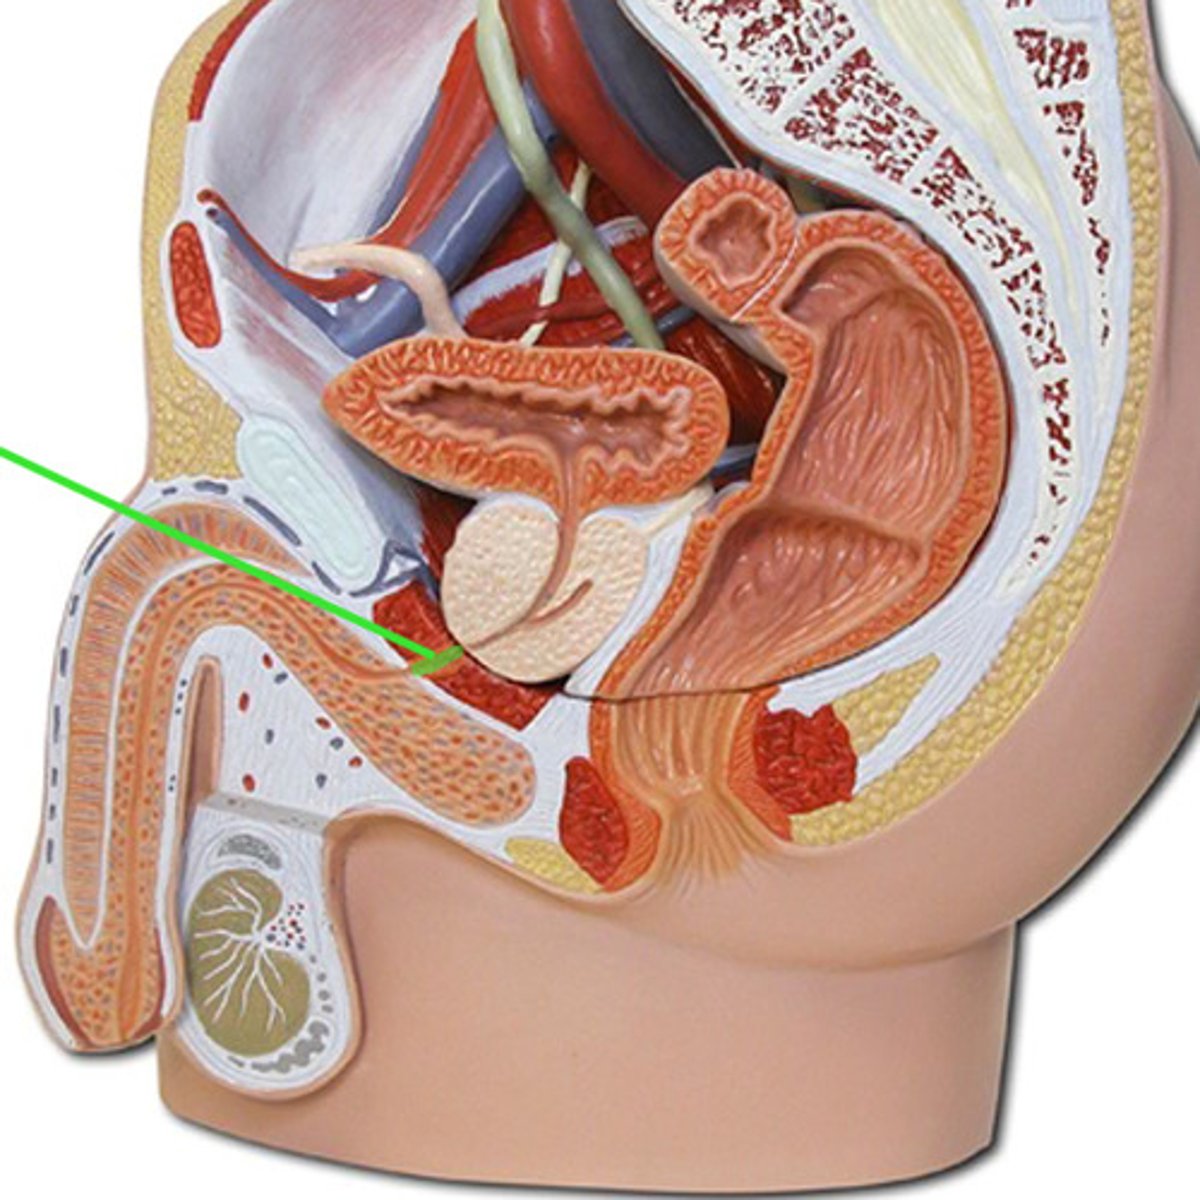

Chapter 30 Anat Phys: Male Reproductive System

Spermatic cord

Ductus deferens

Ampulla (ductus deferens)

Ejaculatory duct

Seminal gland

Prostate gland

Bulbourethral gland